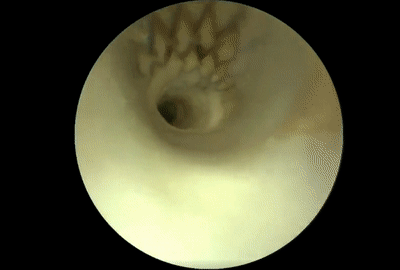

以下是VerAvanti SFE診斷急性大血管閉塞性卒中的影像

VerAvanti SFE演示